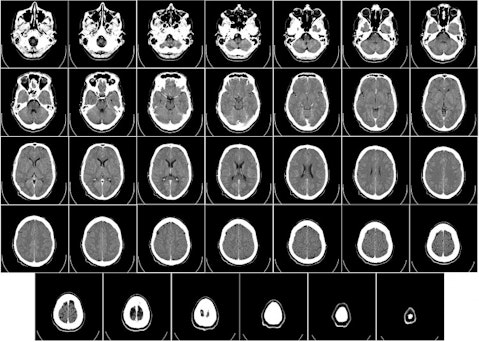

Radiation therapists administer radiation treatment to help fight cancer, including monitoring patients’ progress and reporting this data to the proper medical professionals. They help patients to understand how radiation therapy works by providing explanation and answering questions. They must have the ability to perform X-rays, operate a variety of medical equipment, and report any equipment malfunctions.